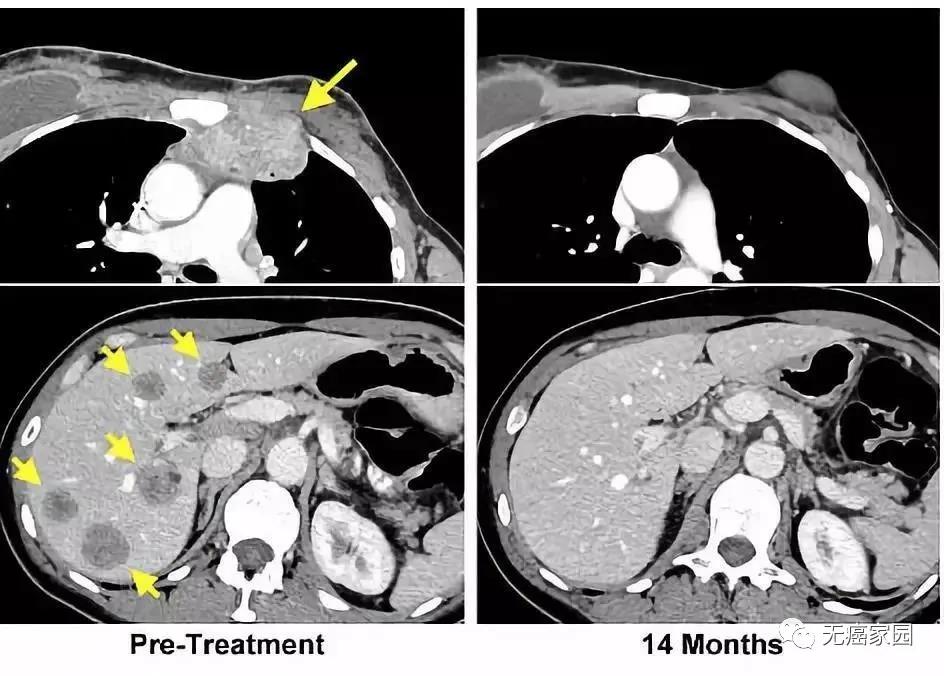

在随后的9个月中,席琳肺部的7个肿瘤中,有6个明显缩小,并最终消失。最后一个对治疗没有反应的肿瘤则通过手术被医生切除。如今,她的体内已经检测不到任何癌细胞了。

这则病例也被刊登在2016年的国际知名医学杂志《新英格兰医学杂志》上,虽然目前TILs疗法在实体瘤中可谓是成绩不俗,但是不得不说这款疗法令致命的晚期KRAS突变的结直肠癌患者肺部7个专业病灶全部消退,属实令人惊艳!